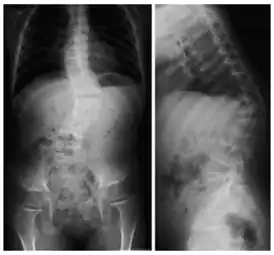

Кифосколиоз

Рентгеновский снимок позвоночника пациента с кифосколиозом. На проекциях хорошо видно искривление позвоночного столба вбок (сколиоз) и выпуклостью назад (увеличенный кифоз) | |

Кифосколио́з (греч. kύφο – согнутый, горбатый и греч. σκολιός – кривой, лат. scoliōsis) – патологическое искривление позвоночника в сагиттальной и фронтальной плоскости, то есть одновременно в переднезаднем и боковом направлениях. Кифосколиоз сочетает в себе два заболевания – кифоз и сколиоз. Может быть как врождённым, так и приобретённым.

При подозрении на кифосколиотическое искривление позвоночника необходимо пройти обследование у ортопеда. Диагноз «кифосколиоз» ставится на основании внешних признаков и данных инструментальных методов исследования. При внешнем осмотре выявляется усиленная сутулость (на поздних стадиях заболевания – горб), сужение грудной клетки и слабость мышц брюшного пресса, различная высота плеч, лопаток, асимметрия таза, видимое отклонение позвоночника от срединной линии при наклоне вперед и расширение межрёберных промежутков на противоположной боковому искривлению стороне. С помощью пальпации спины, шеи и конечностей производится оценка кожной чувствительности, сухожильных рефлексов и симметричности силы мышц. При выявлении неврологических нарушений обязательна консультация невролога. Из инструментальных методов обследования при подозрении на кифосколиоз в первую очередь проводится рентгенография позвоночника, позволяющая определить угол деформации. Наряду с двумя основными проекциями снимки могут выполняться в специальных положениях (лежа, стоя, при растягивании позвоночника). Для уточнения диагноза могут быть назначены методы послойного исследования позвоночника: магнитно-резонансная томография и компьютерная томография. При наличии симптомов нарушения работы внутренних органов может потребоваться дополнительная диагностика и консультация профильных специалистов: кардиолога, пульмонолога, гастроэнтеролога, уролога.